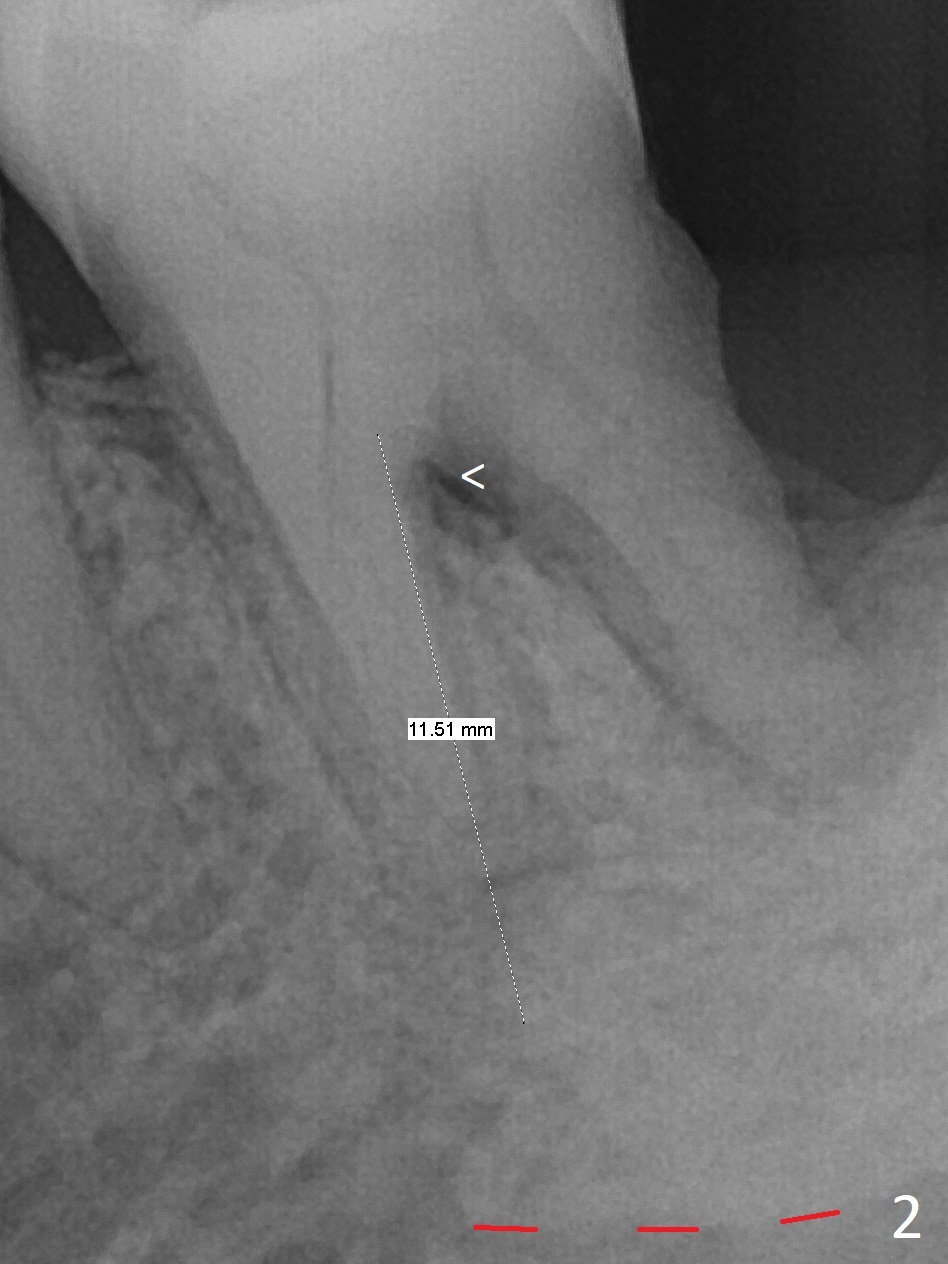

A 68-year-old man returns for extraction of the tooth #19 with distal root periodontal-endodontic lesion (Fig.1 *). After discussion, he agrees immediate implant. A 4.5x11.5 mm implant will be placed in the mesial socket (Fig.2 (red line: superior border of Inferior Alveolar Canal)); the plateau level with the septal crest (<). Osteotomy is initiated in the lingual slope of the mesial socket; the depth is controlled with stopper (Fig.3 S). The implant is placed at the level as expected (Fig.4 <) with insertion torque ~30 Ncm; after placement of 5.7x4(3) mm abutment and Osteogen plug (P) in the apical half of the distal socket, bone graft (G) is placed in the remaining socket gaps, mainly distal and buccal. An immediate provisional is fabricated to keep the graft in place (Fig.5 T). The graft may be lost if the gingival margin recedes in healing. Periodontal dressing is applied for additional security (Fig.6). There is no postop paresthesia. The upper border of the Inferior Alveolar Canal in Fig.3,4 seems to be high. In fact it may be a branch of the Inferior Alveolar Canal (Fig.7 yellow line, as compared to Fig.4). With all of measures taken (including periodontal dressing), the distal bone graft (Fig.8 *) is ~ 2 mm coronal to the crestal bone (red line) 6 months postop. The temporary crown is perforated. The gingival cuff is erythematous. A 6.8x5 mm healing abutment is installed. When the patient returns for impression, a 4.5x5.5(3) mm abutment is fully seated (Fig.9 <). The distal height increases by 4 mm because of immediate implant (support). The mesial papilla remains normal in height and shape immediate post cementation (Fig.10), as related to the mesial socket implant placement without mesial crestal bone loss. The mesial and distal crestal height is maintained 13 months post cementation (Fig.11, weight lifter).